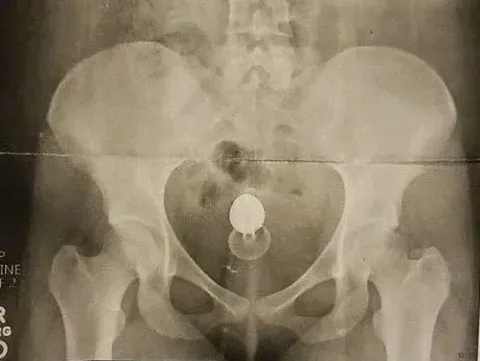

Mereka pun 'bermain-main' dengan sex toy, tapi keintiman tersebut berakhir malapetaka karena sex toy dari jenis butt plugs itu tersangkut di bokong Samantha.

"(sex toy) itu memiliki bebatuan mengkilap, terlihat kecil dan tampak polos. Tapi SALAH," tulisnya di Facebook.

Sebelum melakukan tindakan, dokter melakukan x-ray untuk melihat seberapa jauh mainan seks itu tersangkut. Untungnya dokter bisa mengeluarkan sex toy itu,